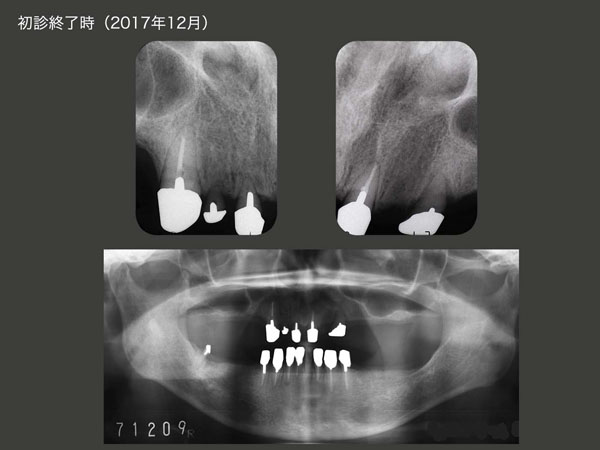

治療途中に骨折等で通院できず,治療期間は延びてしまったが,2017年12月に上下顎にコーヌス義歯を装着した.再植した右上2は動揺があるため側方力をかけないように根面板を装着するに留めた.左上3は若干の動揺があるため,少し丈の短い内冠を装着した.右上1は通常の長さの内冠を装着した.なお,3本の再植歯の歯周ポケットは3mm以下に落ち着いた.

2017年12月,初診終了時のデンタルX線写真およびパノラマX線写真.再植歯の歯根は短いが,歯根膜による歯槽骨の再生がみられた.あとは種々の力に対して抵抗できるか否かであるが,コーヌス冠による2次固定効果により残存歯を束ねたことで,何とか持ちこたえてもらいたい.